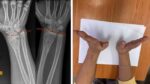

За інформацією: Суспільне. Військовослужбовці 128 бригади провідали врятованого бійця. 128 ОГШБр/Facebook Командир 128 окремої